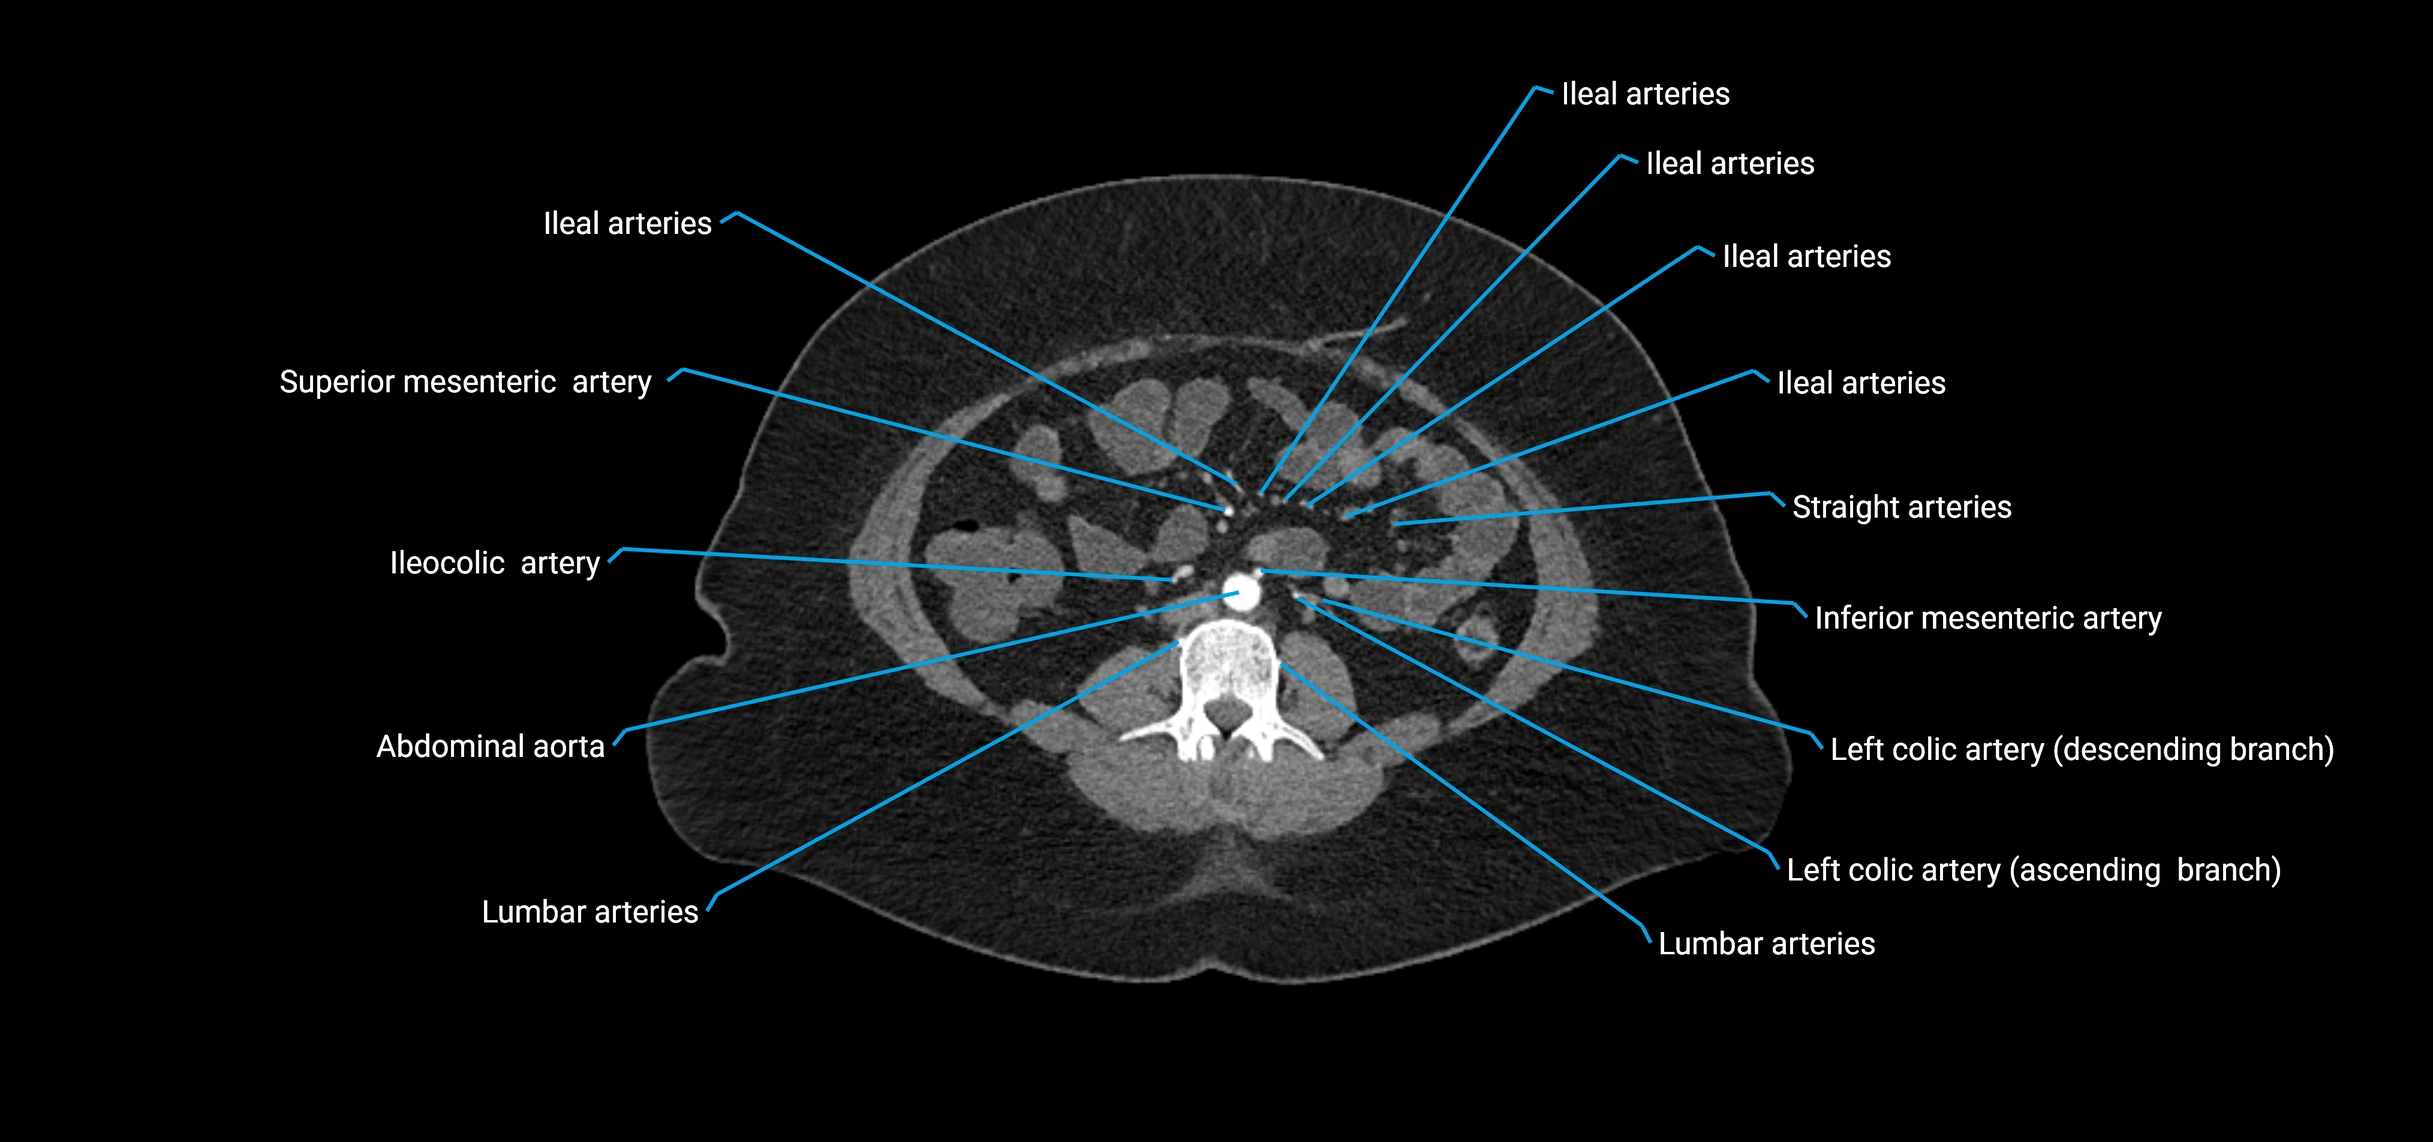

CT images

image

CT Appearance

Non-contrast CT:

• Appears as a tubular soft tissue structure anterior to vertebral bodies

• Calcified atherosclerotic plaques appear as hyperdense foci along the wall

• Useful for screening abdominal aortic aneurysm (AAA) size and mural calcification

Contrast-enhanced CT (CTA):

• Gold standard for abdominal aortic imaging

• Provides excellent detail of lumen, wall, aneurysm, thrombus, and branch vessels

• Multiplanar and 3D reconstructions help in aneurysm measurement, stent graft planning, and dissection evaluation

• Detects acute rupture, traumatic injury, or occlusion with high sensitivity

The abdominal aorta is the continuation of the thoracic aorta, beginning at the level of the aortic hiatus of the diaphragm (T12 vertebra) and terminating at the level of the L4 vertebra where it bifurcates into the right and left common iliac arteries. It lies slightly to the left of the midline and courses anterior to the vertebral bodies, surrounded by the retroperitoneal structures of the abdomen.

The abdominal aorta gives off numerous visceral and parietal branches, supplying the abdominal organs, pelvic structures, and lower limbs. It is the main conduit of oxygenated blood from the heart to the abdomen and lower body. The aorta is clinically significant as the common site of aneurysm, dissection, atherosclerosis, and traumatic injury.

• Unpaired visceral branches: celiac trunk, superior mesenteric artery (SMA), inferior mesenteric artery (IMA)

• Paired visceral branches: middle suprarenal arteries, renal arteries, gonadal arteries (testicular or ovarian)

• Parietal branches: inferior phrenic arteries, lumbar arteries, median sacral artery

• Terminal branches: right and left common iliac arteries